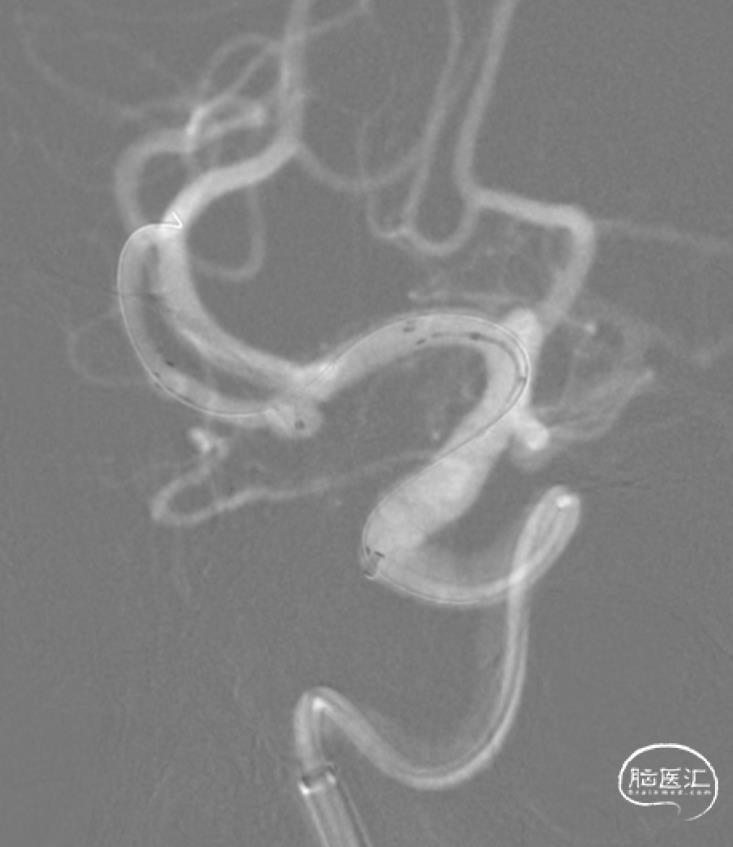

结束前造影。

患者全麻复苏后出室,无神经功能缺损。一切顺利。

本例采用的Y型支架,是第三个技术难点。Atlas开环支架,可以对动脉瘤颈起到较好的保护。但本例动脉瘤与M1分叉后的两大主要分支关系均密切,有可能单侧置入支架的效果仍不满意。考虑到有可能行Y型支架置入,在方案设计时,释放完第1枚支架,便在腔内通过穿网眼技术,将SL-10导管输送至另一分支。这样实际上是在支架和微导管辅助下进行动脉瘤栓塞。由于既往文献和实践中均有弹簧圈脱出甚至移位的报道,加之本例的特殊性,如果撤除SL-10导管,有可能造成此类后果。因此,我们在撤除栓塞微导管后仔细观察,结果发现终末弹簧圈稍有脱出。随即采用Crossing-Y技术释放支架,加强对瘤颈和载瘤血管的保护。动脉瘤栓塞效果满意,瘤颈和载瘤动脉保护良好。